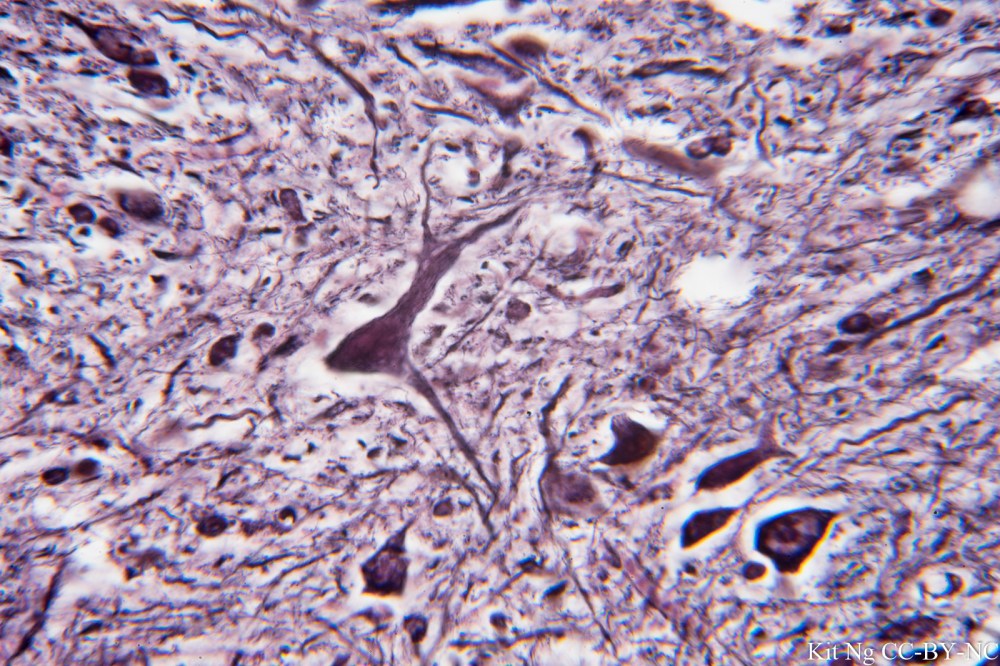

_DSC3409.JPG

Giant motorneuron of the Spinal Cord, trichrome stain.  (TM: 400x, picture taken with a Zeiss F40/0.8 on Sony A7ii)